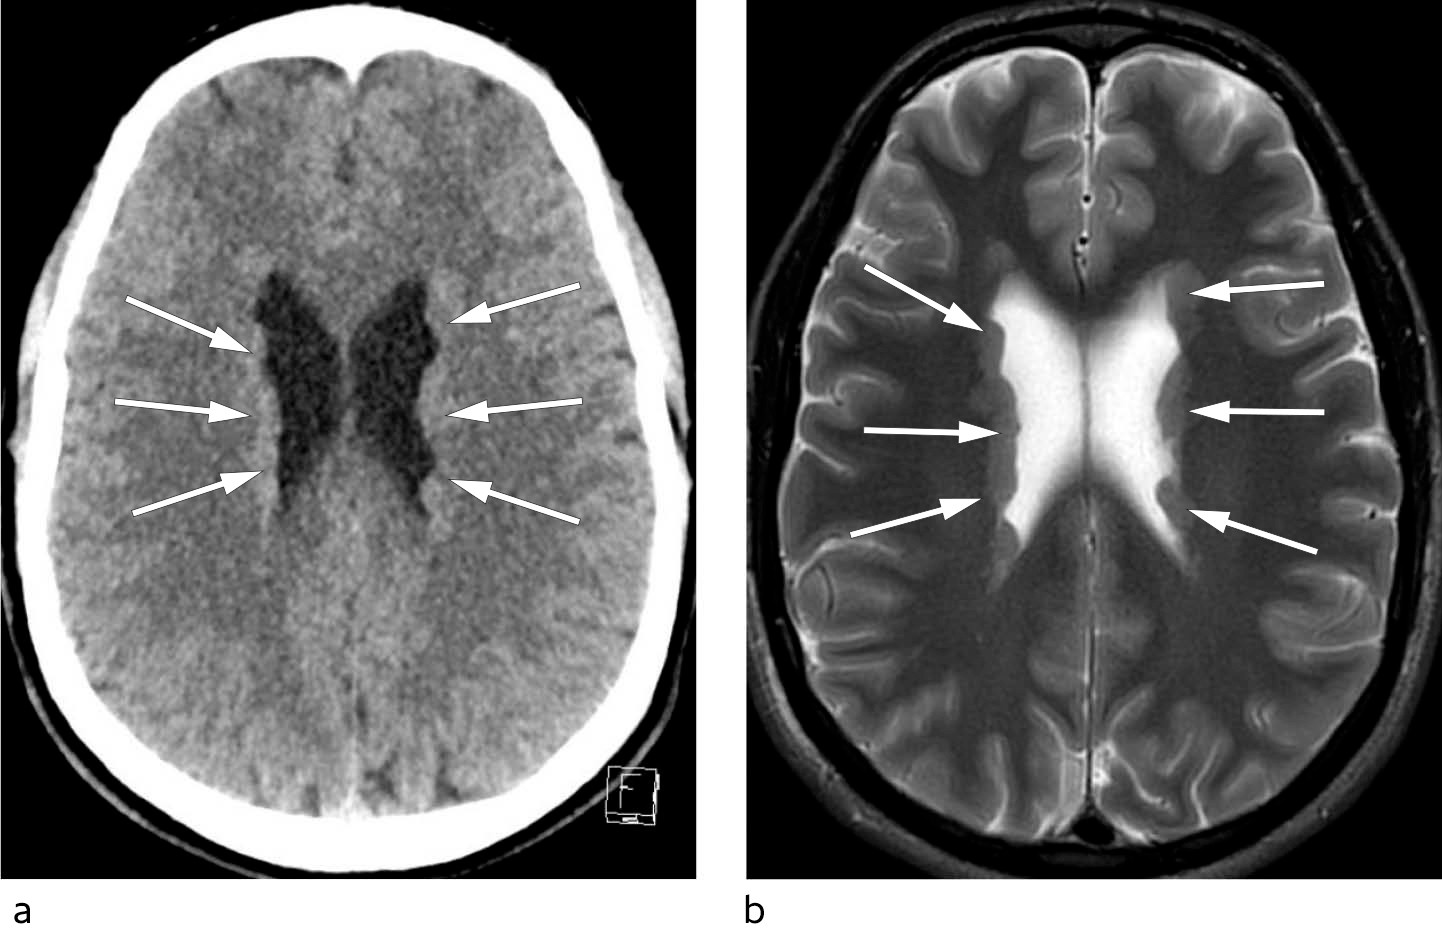

En tidligere frisk mann i starten av 20-årene ble innlagt på sitt lokalsykehus etter et plutselig bevissthetstap som oppstod i stående stilling uten prodromalsymptomer. Det ble observert en tonisk fase under anfallet, men ingen rykninger, tungebitt eller vannavgang. Pasienten var ved bevissthet igjen tre minutter etter anfallet og hadde retrograd amnesi for hendelsen. Han hadde aldri opplevd noe lignende før. Ved innleggelse var det normale funn ved somatisk og nevrologisk undersøkelse. EKG viste ingen avvik og ble vurdert som normalt. Cerebral CT ga mistanke om bilateral periventrikulær nodulær heterotopi (figur 1). Dette ble senere bekreftet med cerebral MR, som er den foretrukne modaliteten ved utredning av denne tilstanden.

Hos vår pasient avdekket billedundersøkelsen et funn som var avgjørende for å kunne stille riktig diagnose. Heterotopi av grå substans er en relativt sjelden utviklingsforstyrrelse med svekket nevronal migrasjon i embryogenesen (3). Tilstanden kan deles inn i nodulær og diffus type. Nodulær heterotopi kan videre klassifiseres som subkortikal eller periventrikulær. Tilstanden er forbundet med andre malformasjoner i sentralnervesystemet, blant annet i hippocampus. Pasientene har som regel normal intelligens. Den vanligste kliniske presentasjonen er fokal og multifokal epilepsi, som i de fleste tilfeller debuterer i ungdomsårene. De periventrikulære nodulære heterotopiene opptrer som foci for unormal nevronal aktivitet. EEG-registrering med dybdeelektroder har vist epileptisk aktivitet utgående fra disse nodulene, og anfallslidelsen antas å stamme fra heterotopien hos de fleste rammede (3). Vanlig årsak er mutasjoner i filamin 1 (FLNA)-genet som er lokalisert på X-kromosomet, men tilstanden forekommer også sporadisk og ved andre genmutasjoner (4). De fleste med X-kromosombunden sykdom er kvinner. Da FLNA-mutasjoner er assosiert med hjerte- og karlidelser (5), bør supplerende kardiologisk utredning vurderes. Vanlige manifestasjoner er defekter i hjerteklaffapparatet og proksimale aorta (6).